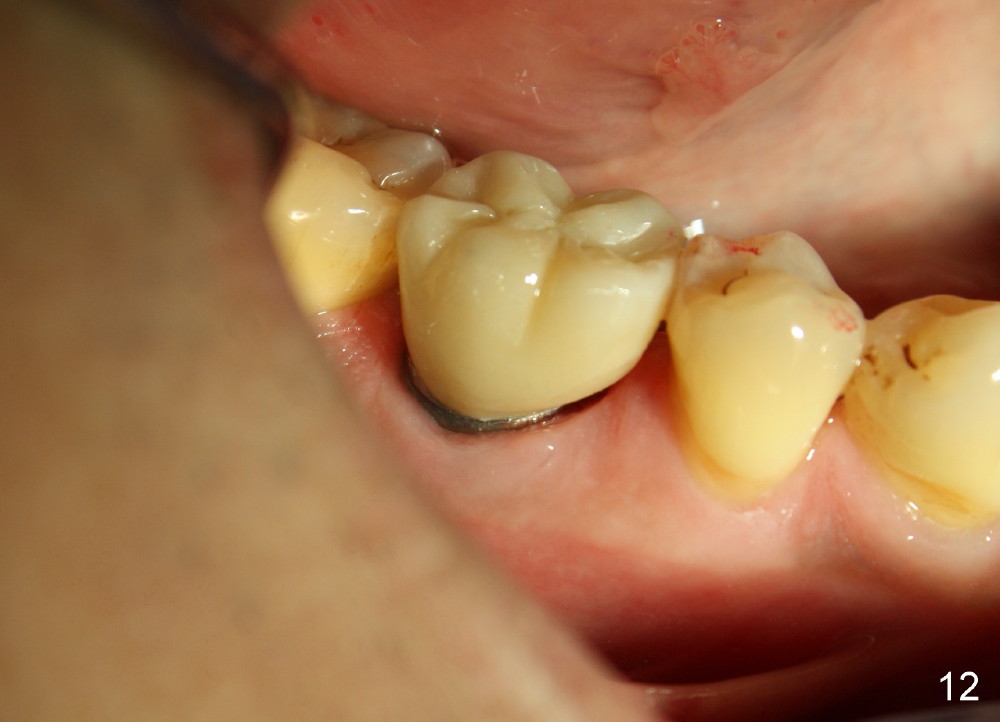

The distal socket is closed completely with suture, whereas the mesiobuccal space is partially closed with collagen gauze and suture (Fig.8 *). The wound is then covered by perio dressing. The gingiva heals around the implant 18 days postop (Fig.9). Three months postop, the implant is stable. The mesial upper portion of the threads appears to have better contact with the bone (Fig.10 <, as compared to Fig.7); the density of the distal socket seems to increase (*). There is no buccal plate atrophy (Fig.11 ^). Supragingival margin is designed for the crown to prevent periimplantitis (Fig.12)

When a large implant is placed in a molar socket, one dimension of the remaining socket is small (buccolingual for lower, mesiodistal for upper). It is apparent that the mandibular buccal and lingual gingiva is relatively loose for the most time, the mesial and distal socket could be closed by suturing and perio dressing. The maxillary palatal gingiva is particularly thick and tough to be approximated. It appears necessary to develop a technique using an immediate provisional to close the socket or place an abutment. Cortex-like bone seems to have grown into the mesial thread spaces 3 years post cementation (Fig.13 <). The 7x17 mm implant was placed buccal (Fig.14 B). The slowly resorbed buccal plate seems to darken the buccal gingiva (Fig.15 B). The bone next to the implant is dense 6 years post cementation (Fig.16 *). The implant at 19 should be smaller and placed lingual.